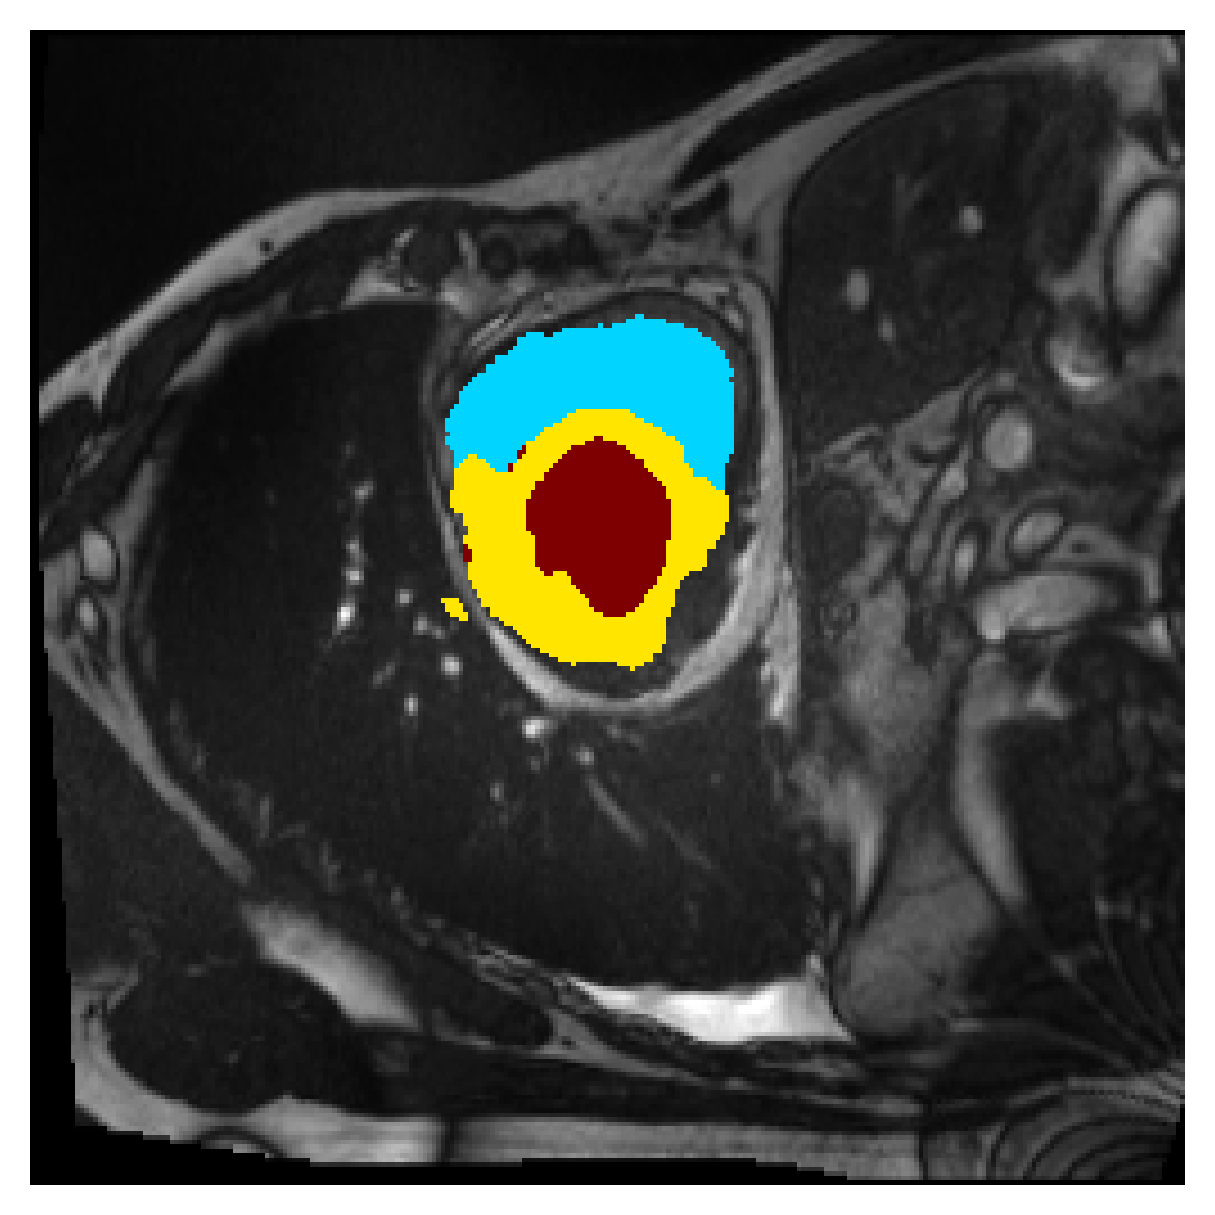

Qualitative comparison

| (a) Ground truth | (b) , full | (c) , weak | (d) |

| (full) | supervision | supervision | |

|

|

|

|

|

|

|

|

|

|

|

|

| (e) | (f) | (g) | (h) CRF-loss |

In Figure 6 we provide qualitative results on a number of randomly chosen test set slices. Upon visual inspection, we can observe that training with the intensity-aware distances (particularly with and ) follows the image gradients better and is better at recovering the underlying shape than the Euclidean version. The CRF-loss seems to recover the shape of the myocardium and left ventricle to some extent, but fails entirely on the right ventricle.